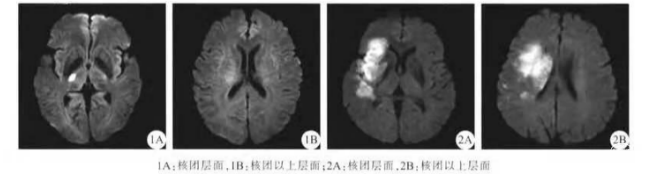

DWI-ASPECTS评分基于弥散图像大脑中动脉 供血区2个层面上的10个区域:(1)核团层面(即丘脑和纹状体平面):划分为M1、M2、M3、岛叶、豆状 核、尾状核和内囊后肢7个区域,M1、M2、M3分别 为:前部皮质、岛叶外侧的皮质和后部皮质;(2)核团 以上层面(在核团水平上方2 cm):占3个区,分别记 为M4、M5和M6,为M1、M2和M3相对应的上 部。总分10分,每累及1个区域减去1分。

DWI-ASPECTS在进行缺血性存在溶栓中的应用

ASPECTS是2000年Barber等制定的一种简单、可靠和系统评估大脑中动脉区早期缺血性变化的半定量评分系统。

急性前循环脑梗死患者DWI上显示的病变范围对预后具有预测作用。DWI-ASPECTS分值与DWI上病灶体积具有较好的一致性。

当DWI-ASPECTS分值为7分时,病灶体积为70 mL;当DWI-ASPECTS分值4分时,病灶体积为100 ml。

尽管DWI-ASPECTS不能完全替代体积的测量,但其却能提供一些半定量估计,正被越来越多地用来评估患者情况及其预后。